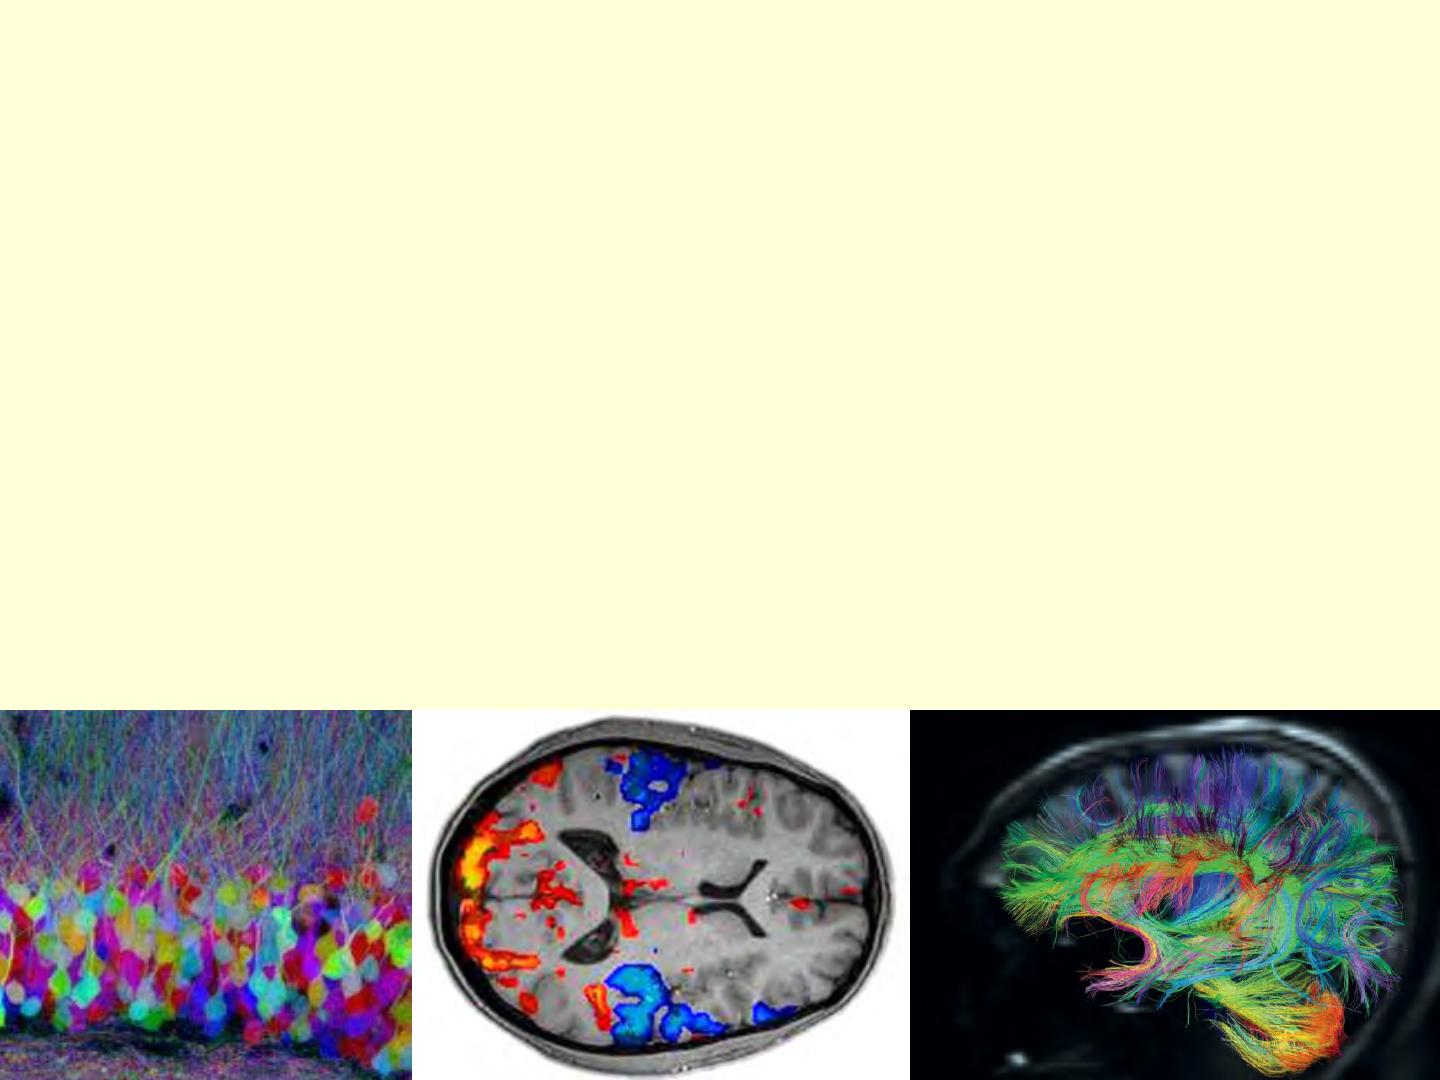

Voir le cerveau en couleur

pour le cartographier

Comment retracer le trajet des axones dans le cerveau ?

Avec des animaux, on utilise des techniques de traçage,

basée la capacité qu'ont les neurones de faire circuler des molécules

dans leur axone (le " transport axonal ").